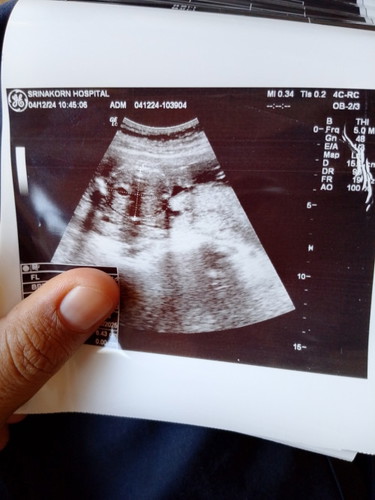

สอบถามค่ะ ภาพอัลตร้าซาวน์ของโรงพยาบาลรัฐทำไมมองไม่ชัดหรือว่าเป็นที่เครื่องมือค่ะ พยายามมองแล้วค่ะแต่มองไม่เห็นเลยค่ะ แต่หมอบอกน้ำหนักตามเกณฑ์ทุกอย่าง แต่มองไม่เห็นว่า หญิง หรือ ชาย#ขอบคุณล่วงหน้าสำหรับความคิดเห็นค่ะ

ในรูปเขาวัดขนาดน้ำหนักน้องค่ะ ไม่แน่ใจว่า ใช่หัวน้องไหม ยังโชคดีนะคะ ได้รูปมาด้วย บางที่โรงพยาบาลรัฐเขาไม่ให้นะคะ เขาซาวด์เองดูเอง และจะซาวด์แค่2ครั้งเท่านั้น ที่เหลือทุกครั้งคือฟังเสียงหัวใจอย่างเดียว ถ้าคนไม่ได้ผิดปกติอะไร

Ultrasoundมี หลายมิติค่ะ ส่วนใหญ่รัฐบาลจะเป็น 2 มิติ จะเห็นไม่ค่อยชัดแบบนี้ค่ะ เอกชนจะเป็น3มิติหรือ4มิติ จะเห็นลูกชัดกว่า ค่ะ ถ้ายัง งง หาgoogle ได้ค่ะ

อันนี้คือหัวน้องค่ะ ในภาพีอน้องนอนหงาย หมอวัดขนาดและน้ำหนักน้องค่ะ ถ้าซาวเพศจะเป็นแบบนี้ค่ะ